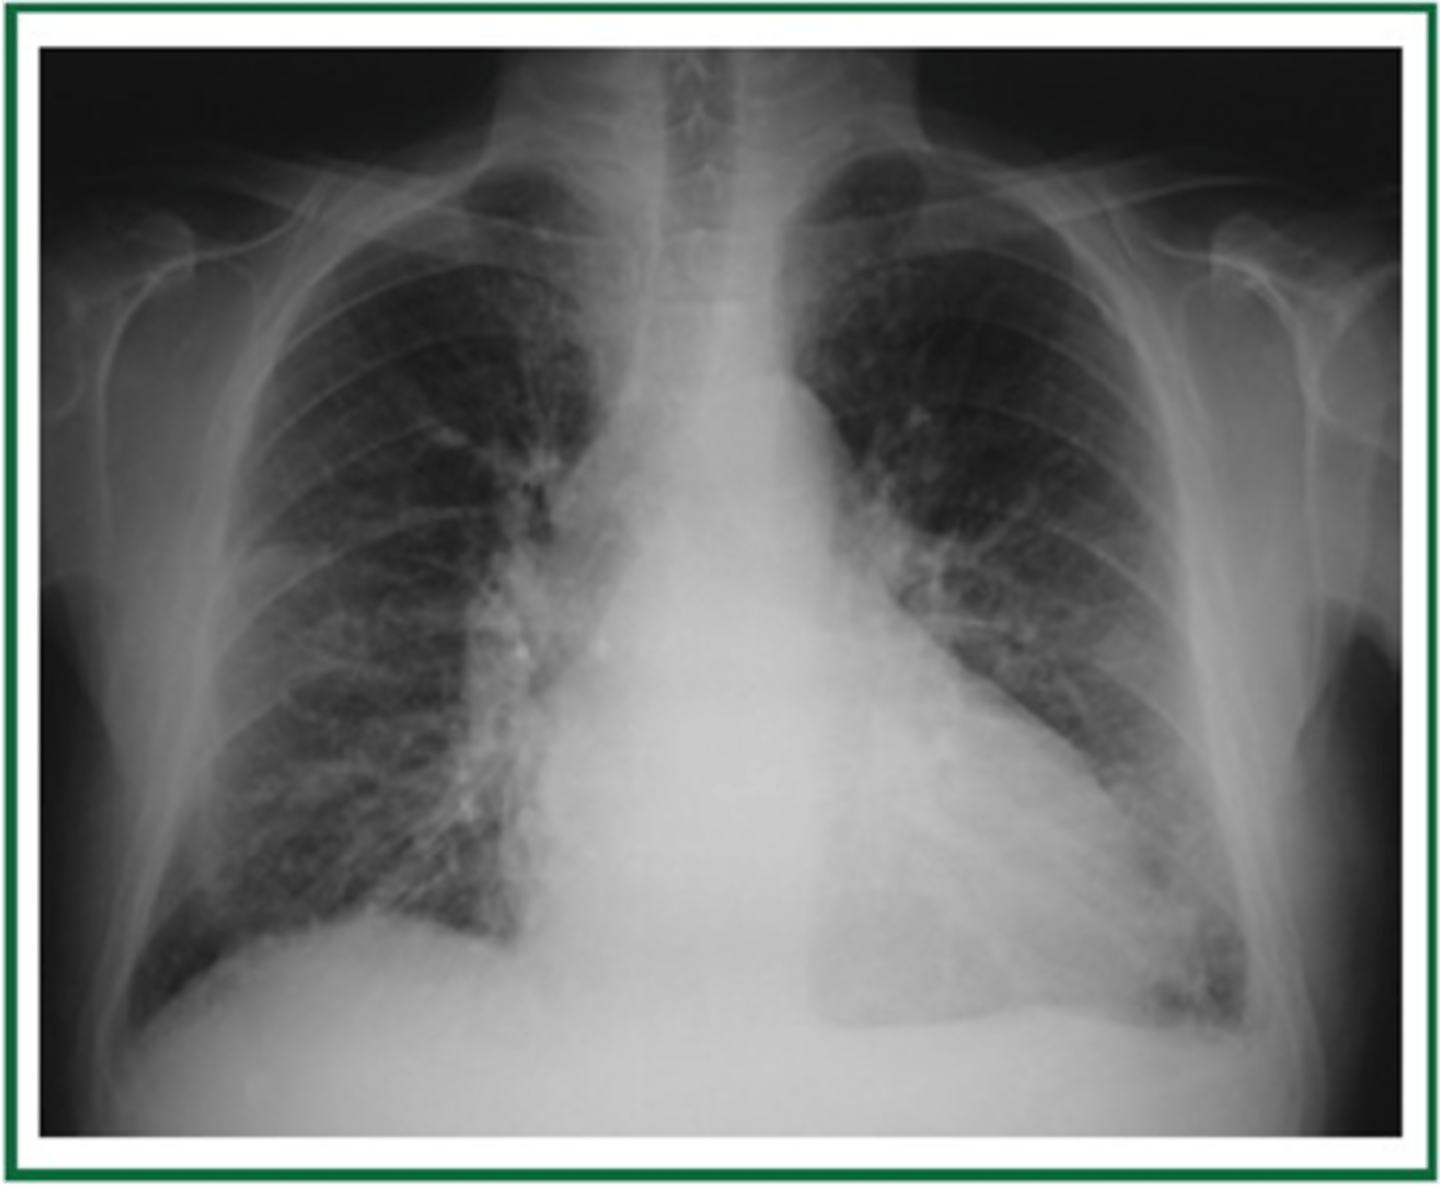

Walls of the bronchi thickened by inflammation or infection, may be diffuse or focal

Bronchiectasis

CXR in affected individuals is often normal or shows non-specific findings

knowt flashcard image

Tram track lines